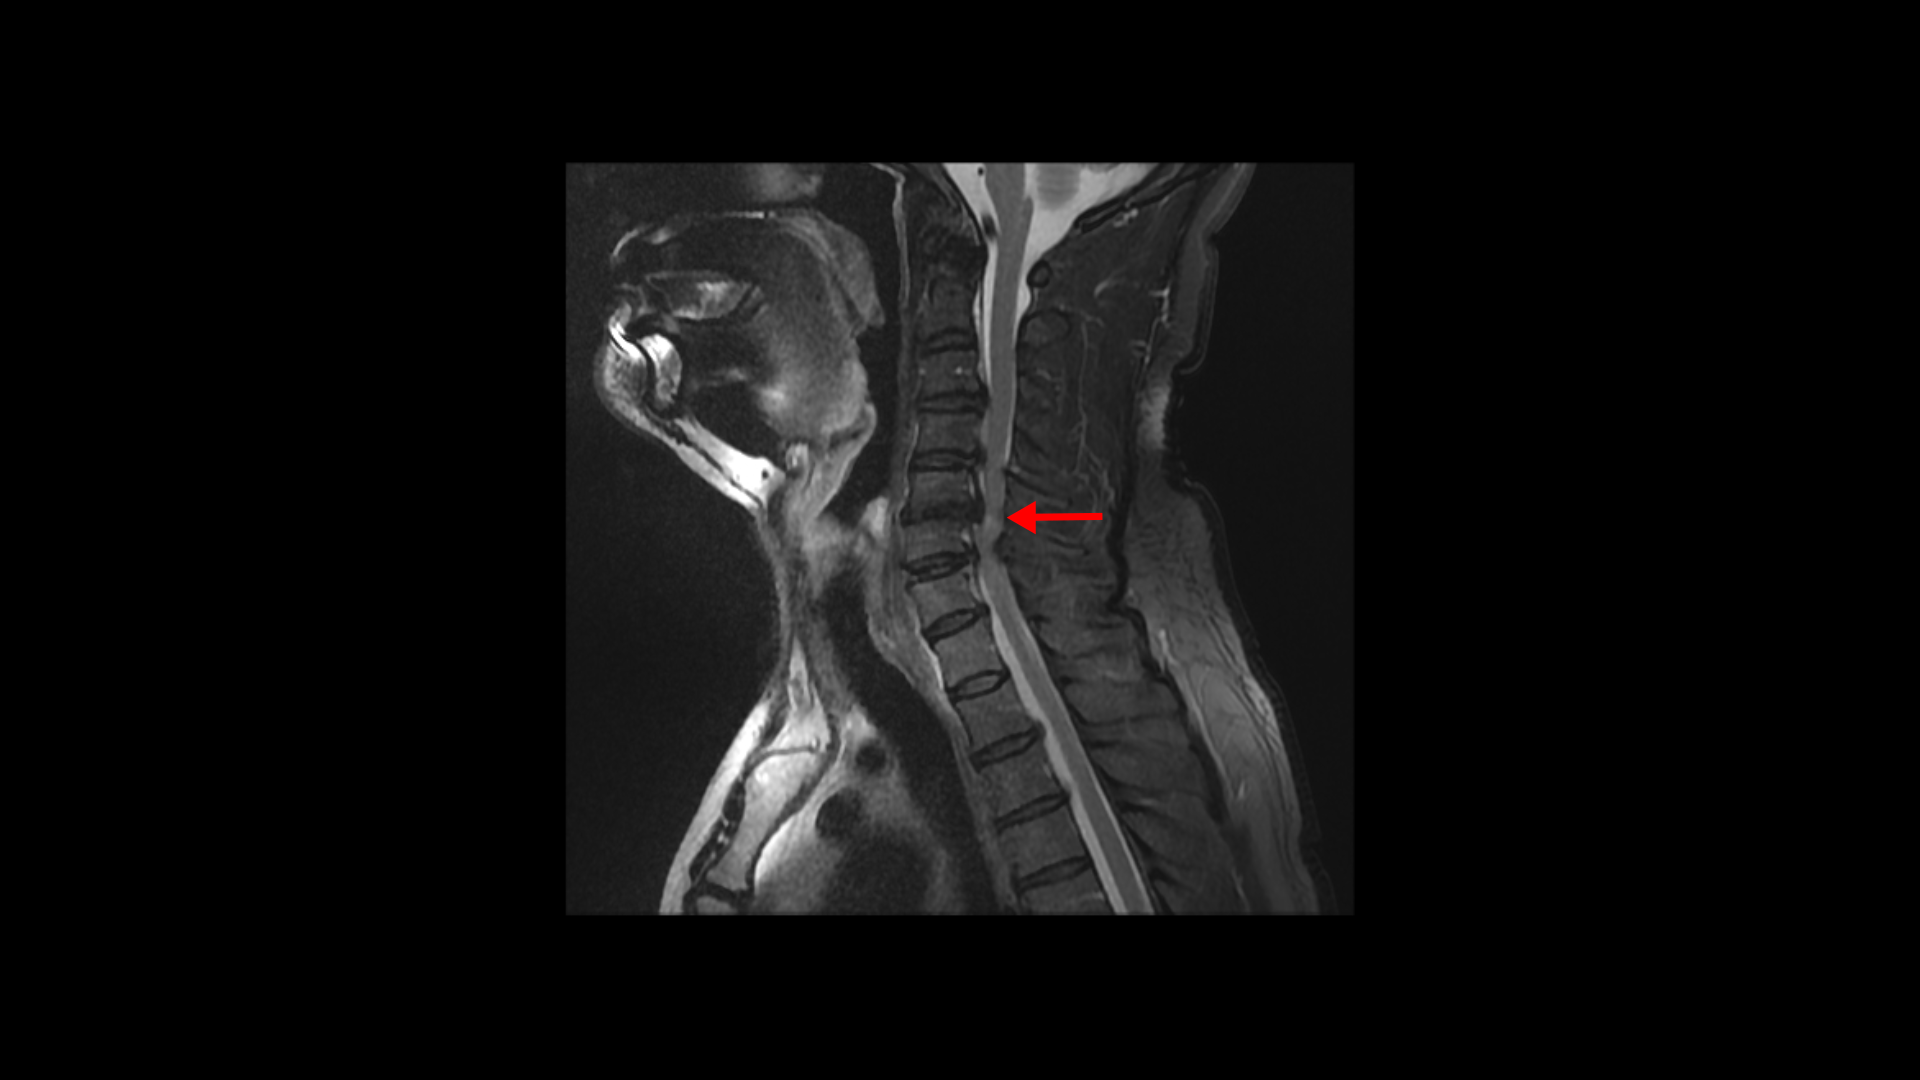

팔의 통증과 저림, 숟가락질과 젓가락질이 어려운 경추척수증 환자분의 MRI 상태 및 증상은?

이 환자분의 목에 7~8년 전에 심한 목디스크 파열이 발생하였습니다. 오른 팔이 극심하게 아팠고 디스크 파열이 너무 심하고 척수증까지 있어서 수술 권유를 받았으나 주변의 만류로 수술은 받지 않고 물리치료와 신경 주사만 맞으면서 버티셨습니다.

이분 MRI에서 보시다시피 전체적으로 목의 한마디만 제외하고 여러 마디가 다 안 좋습니다.

목의 3번 4번과 4번 5번에는 가운데 쪽으로 디스크 돌출이 있고

5번 6번 문제가 제일 심각한데, 가운데 우측으로 목디스크 파열이 심하게 있습니다.

오른쪽으로 보시다시피 신경 나가는 길이 디스크와 협착으로 많이 막혀 있고 척수 신경에는 경추척수증, 즉 척수신경의 손상이 보입니다.

6번 7번과 7번 흉추 1번 디스크도 가운데로 밀려 나와있습니다.

이 환자분의 오른쪽 팔의 통증과 젓가락질이 안 되는 증상은 척수증보다는 목디스크 파열과 경추협착으로 인한 증상으로 보입니다. 즉 척수증은 있지만 척수증 관련된 증상은 없어 보입니다.